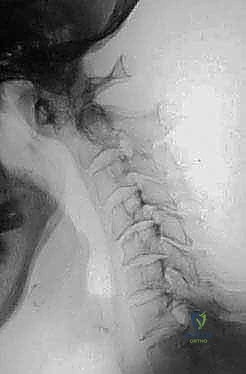

FIG 3 • E. Extension lateral radiographs demonstrate C1–2 instability in a patient with rheumatoid arthritis.